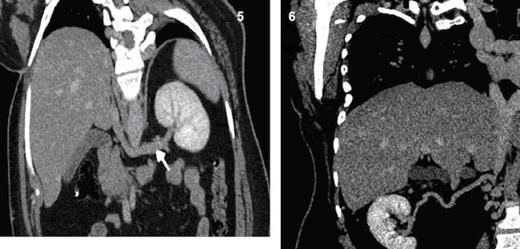

Dilated and tortuous azygous & hemiazygous veins (Fig. 2), with multiple prevertebral and paravertebral collaterals (Fig. 3) as well as superificial collateral veins in the abdominal wall (Fig. 4) were seen. Left renal vein is draining into the hypoplastic segment of IVC (Fig. 5).

Coronal MPR CT image shows a long left renal vein seen draining into the intra-hepatic segment of IVC. Fig. 6 Coronal MPR CT image shows a right renal collateral vessel draining into hypoplastic segment of IVC.

The right renal vein is absent represented by long tortuous collateral draining into hypoplastic segment of IVC (Fig. 6) and multiple collaterals draining into the retroperitoneal venous plexus (Fig. 7). The right great saphenous vein exhibits drainage into the distal part of right common femoral vein (Fig. 8).